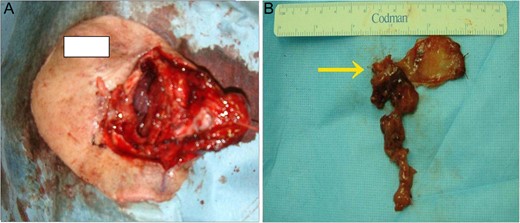

An extranasal approach (lateral rhinotomy) was performed under general anesthesia. To obtain good visualization, the anterior wall of the right frontal sinus was also opened. The tumor had a pedicle on the right nasal septum near the olfactory cleft, which we extirpated totally, leaving an adequate free margin (Fig. 3A and B). The thick mucous recognized in the ethmoidal sinus proved to be non-malignant.

(A) After wide surgical excision (B) gross specimen. The tumor with a pedicle on the right nasal septum near the olfactory cleft was extirpated totally, leaving an adequate free margin. (arrow: pedicle of tumor).